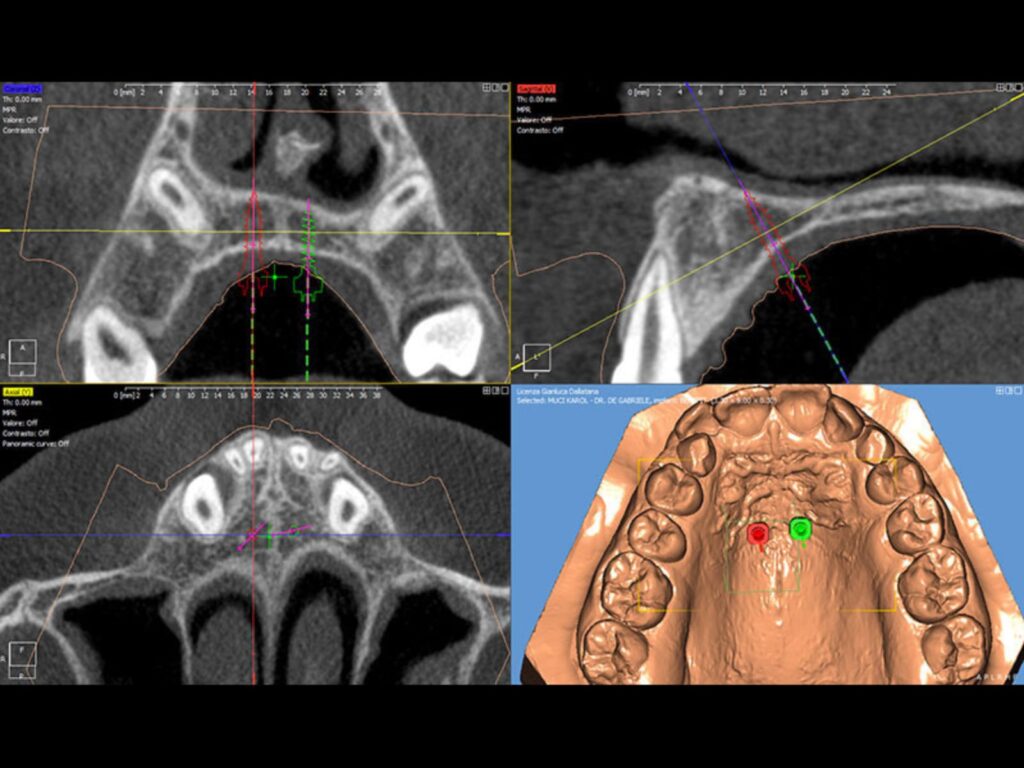

Notre cabinet utilise le système EASYDRIVER®, une technologie numérique avancée qui permet de positionner les mini-vis orthodontiques avec une précision et une sécurité maximales. Ce système combine des radiographies 3D (Cone Beam) et des modèles numériquestridimensionnels, permettant de planifier avec une précision millimétrique le placement des mini-vis BENEfit®.

Grâce à un logiciel dédié et à un guide chirurgical personnalisé, fabriqué sur mesure à partir d’une simple empreinte, il est possible d’effectuer l’intervention avec une sécurité, une exactitude et un confort optimaux pour le patient.

Protocole Easy Driver®

• Empreinte traditionnelle ou via scanner oral

•Appariement du modèle avec la CBCT (Cone Beam) ou la téléradiographie latéro-latérale

•Localisation du site pour les mini-vis* BENEfit®

•Confirmation du projet par le clinicien

•Réalisation et livraison du guide (dima) et de l’appareil orthodontique grâce au brevet européen EP 3 364 912 B1